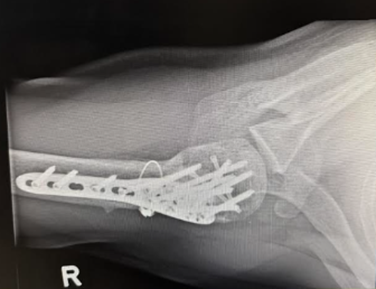

We present a 50-year-old Southeast Asian male who presented to the emergency department with right shoulder pain and deformity. This closed injury was sustained after colliding with a rock while cycling, in which the patient fell off his bike and landed onto his right shoulder. Neurovascular status was intact, and radiographs of the right shoulder revealed a 4-part right proximal humerus posterior fracture-dislocation with head split (AO Classification 11-C3) (Image 1). During the consultation, the options of surgical fixation and hemiarthroplasty (HA) were both explained to the patient. The risk of AVN leading to salvage arthroplasty was discussed for fixation, whereas the concerns of implant longevity and dislocation risk was discussed for arthroplasty. In view of the displaced fracture, shared decision making between surgeon and patient was made for surgery to facilitate early mobilisation. Considering the patient’s age and activity level, fixation will be attempted. However, the patient was counselled on the possibility of shoulder hemiarthroplasty should the intraoperative findings reveal a fragmented fracture pattern to prevent AVN, or an unfavourable fracture pattern in which fixation is unlikely to be successful. One key limitation of Hertel’s study to predict the risk of AVN is the presence of few young patients (mean age of the study participants were 60 years old) [18]. This also influenced the surgeon’s decision to offer joint preserving surgery to the patient. A computed tomography scan was not necessary since the severity of the fracture-dislocation is evident on radiographs.

Image 1: Preoperative imaging of the right shoulder showing a right proximal humerus posterior fracture-dislocation with head split.

The patient underwent open reduction internal fixation (ORIF) on post-injury day 11. Following a deltopectoral approach and biceps tenodesis, the 4-part PHFD was seen. The humeral head was posteriorly dislocated and impacted upon the posterior glenoid with a nondisplaced head split. The greater tuberosity fragment was identified with an intact supraspinatus However there was an avulsion of the subscapularis off the lesser tuberosity. The humeral head was reduced with judicious soft tissue management and assessed in-situ to prevent secondary injury and ischemia. The articular block was secured with 2 headless compression screws. The neck-shaft angle was restored using plate-assisted reduction and an angular stable construct was achieved with an anatomical locking compression plate (Synthes PHILOSTM). To prevent varus malunion, the height of the plate was determined on fluoroscopy (Image 2) to enable the inferomedial ‘kickstand’ screw [31]. The medial calcar was reduced and cerclaged to the plate for bony apposition and increased fixation strength. Cement augmentation (Stryker Hydroset) was performed. Transosseous repair of the Subscapularis was done with closure of the rotator interval.

Image 2: Intraoperative fluoroscopy demonstrating satisfactory anatomical reduction of the 4-part proximal humeral posterior fracture-dislocation.